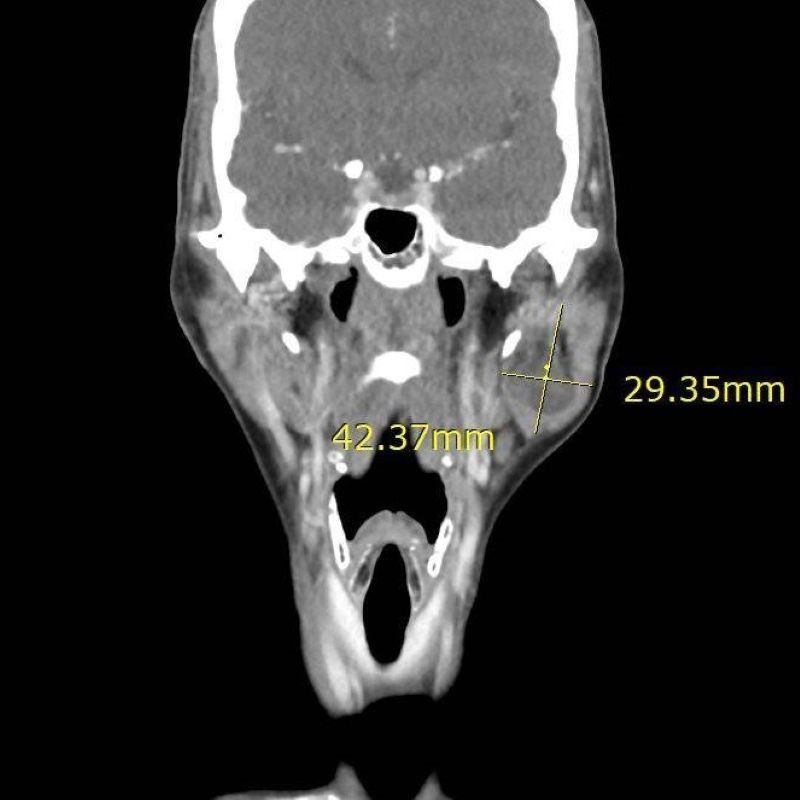

影像顯示其臉頰有約4公分大的腮腺腫瘤。